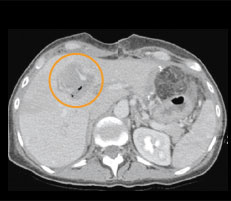

Abb. 1c

Verlaufskontrolle nach vier Monaten: Zwischenzeitlich wurde der rechte Leberlappen, wo sich die restlichen Metastasen befanden, entfernt (siehe Pfeile entlang der Operationslinie: Resektionsrand der Leber). Auf der linken Seite ist das nachgewachsene Lebergewebe ohne Vernarbung sichtbar.

Vier Monate nach der IRE-Anwendung kommt Frau O. zur Verlaufskontrolle. Die computertomographische Kontrolluntersuchung verdeutlicht, dass die Narbe im Bereich der vormaligen Ablationszone und die Metastase in der Zwischenzeit verschwunden sind und sich das Lebergewebe vollständig regenerieren konnte (Abb. 1c). Mit der Kombination aus Operation und Ablation mittels irreversibler Elektroporation konnten trotz des Befalls beider Leberlappen alle Metastasen entfernt werden. Frau O. gilt als geheilt und tumorfrei.